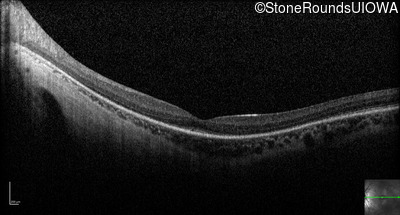

Optical Coherence Tomography - Left - 20/50 -1

Exemplar / OCT Stack